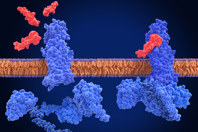

Cell therapy’s future depends on smarter gene delivery. Learn how lipid nanoparticles offer a scalable, cell-friendly alternative to electroporation and viral vectors for manufacturing efficiency.